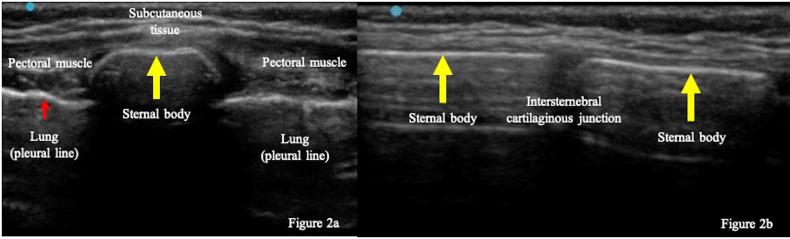

A previously healthy, 4-year-old boy visited our emergency department due to chest pain after a fall from a skate scooter. Physical examination revealed tenderness over the sternal body. Point of care ultrasound (POCUS) of the sternum demonstrated a discontinuation of a hyperechoic structure of the sternal cortex, suggesting a sternal fracture. POCUS did not detect intraperitoneal fluid, pericardiac effusion, or pneumothorax. Plain radiograph confirmed the diagnosis of isolated sternal fracture and the patient was discharged with conservative treatment. POCUS was useful not only in diagnosing a sternal fracture but also to rule out concurrent injuries.